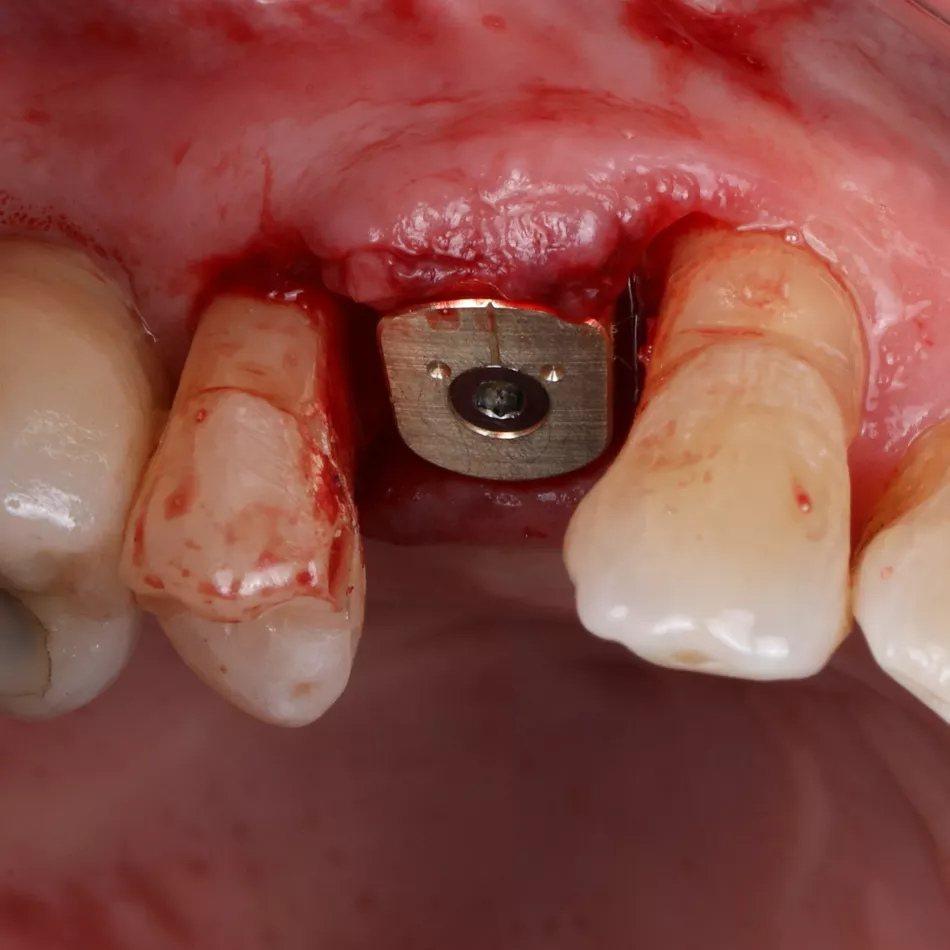

Phase III: Guide design (Fig 3a. 3b. 3c) for guided Implant Placement and Soft-Tissue Augmentation

After healing, implant placement was performed using a tooth-supported surgical guide under local anaesthesia. A limited buccal flap allowed visual control and creation of a pouch for a connective tissue graft. Osteotomy was completed with the Integral surgery kit, and a 3.4×12 mm Axiom® X3 implant (XT34120) was placed under fully guided conditions with a Healfit® SH (OPSHSC23) healing abutment connected. A palatal connective tissue graft was positioned buccally to enhance soft-tissue thickness. The flap was sutured with 5-0 interrupted and mattress sutures. Postoperative care mirrored Phase I, with uneventful healing observed (Fig 4 a&b).

4a. 4b. Lateral view showing Healfit® SH healing screw connected to the implant and occlusal view of sutures for tension-free closure.